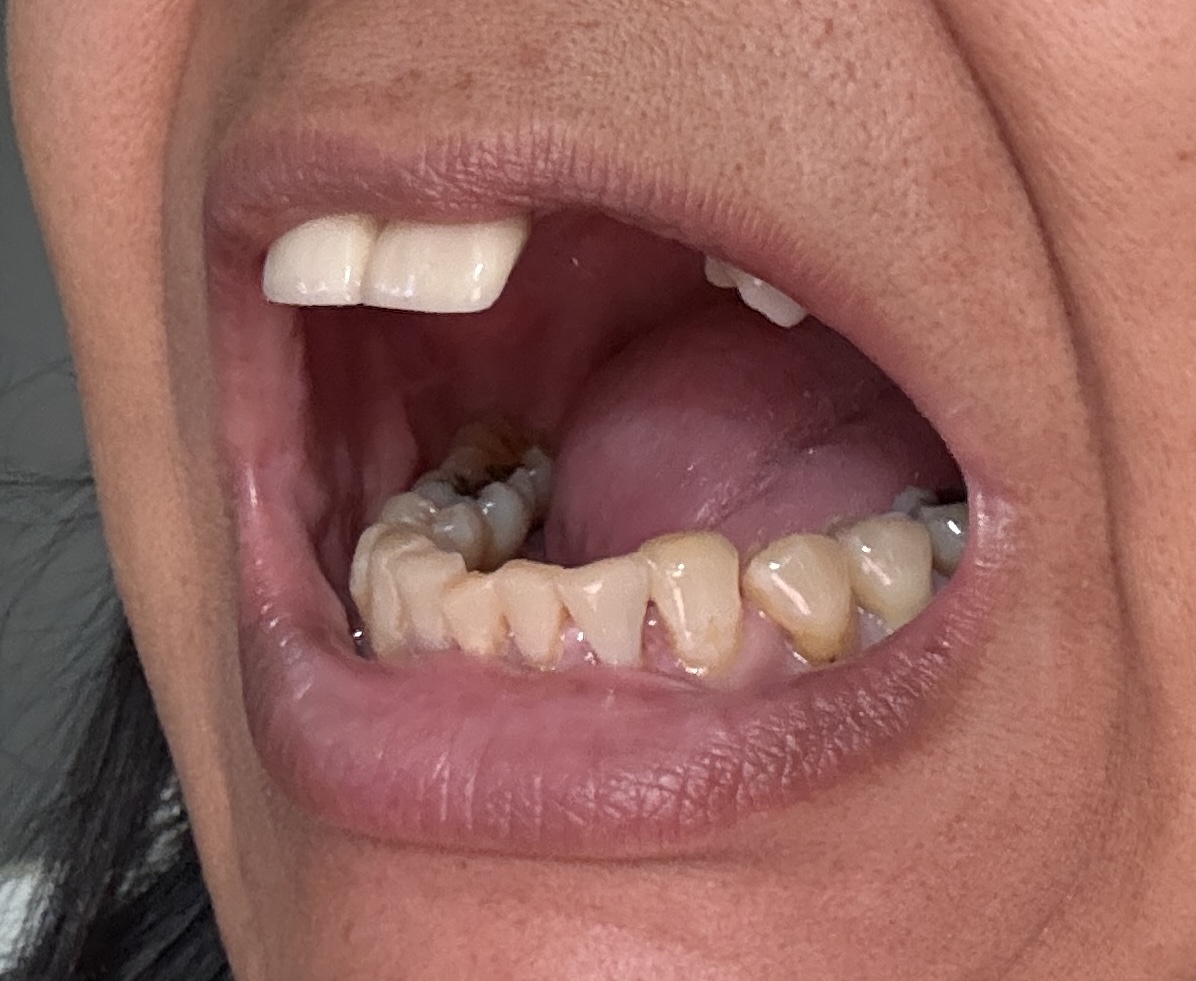

Dental Auction No. 11561: Several extractions and All-on-4 Top and bottom arches

12,13,14 have had root canals in past and now have quite a bit movement. 2-5 have all had root canals in past and now the crowns are breaking down.

Overall, all of my gums have receded and most of the bottom teeth are exposed w/ some roots and there are many cavities.